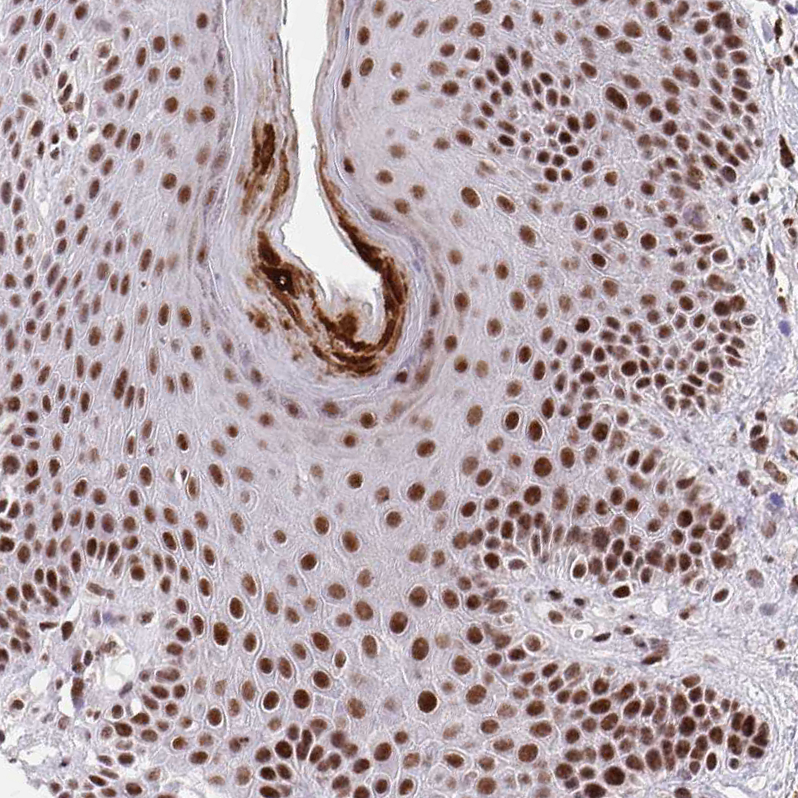

Immunohistochemical staining of human prostate shows strong nuclear positivity in glandular cells.